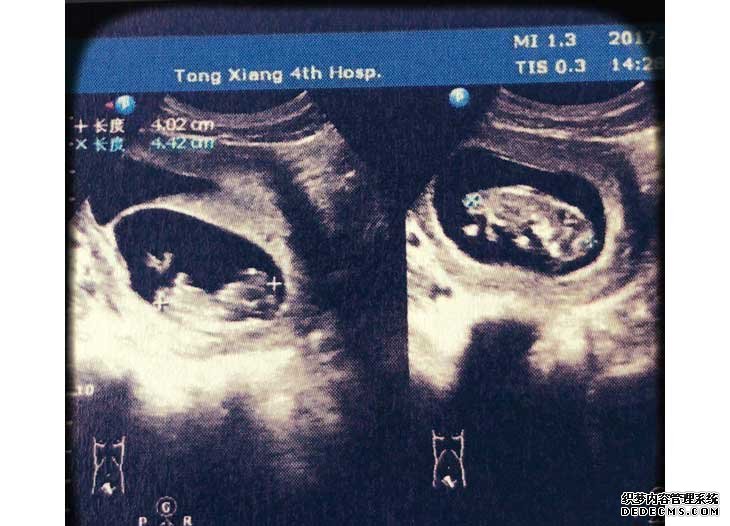

那几天也就安心地躺在床上,小心翼翼地。一回国后大概过了14天左右,进行验血,结果血值翻倍8080,心想有可能双胎,终于熬到B超的时候,大夫也说双胞胎,都有了胎心,那一刻还是懵的,回家缓了几天,失眠了几天,突然有了前所未有的喜悦。V2G育儿资讯网-育儿常识全方位解读,助您开启好孕之旅